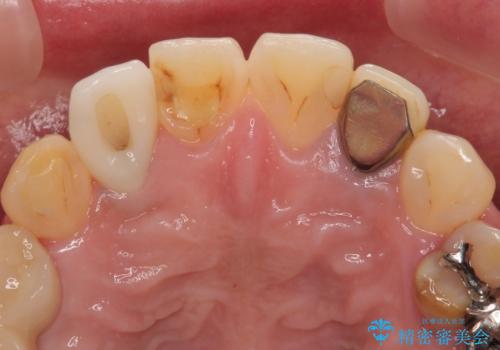

- 歯が破折しているため、抜歯が必要であると近医で診断されてからも放置を続けてしまったとのことで来院された患者様です。

セオリーとしては、インプラント補綴治療により奥歯の咬み合わせを確立してから、前歯部の処置を行うことになりますが、初めてのインプラント治療であることや、前歯部の見た目が気になっていることから、前歯の抜歯即時埋入インプラントによる補綴治療を先行して行い、並行して奥歯のインプラント治療を進めて行くこととしました。

抜歯即時埋入インプラントによる補綴治療の特徴は、短期間であることや処置数が少ないことが挙げられます。また、表側の歯肉の陥凹を避けることができるというメリットがあります。しかしながら、今回は歯根破折の程度が酷く、やや膨らみを失うこととなりましたが、スムーズに治療を終えることができました。

臼歯部は前歯以上に炎症が酷く、抜歯即時埋入不可と判断されましたが、従来法よりは短期間で終えることができました。